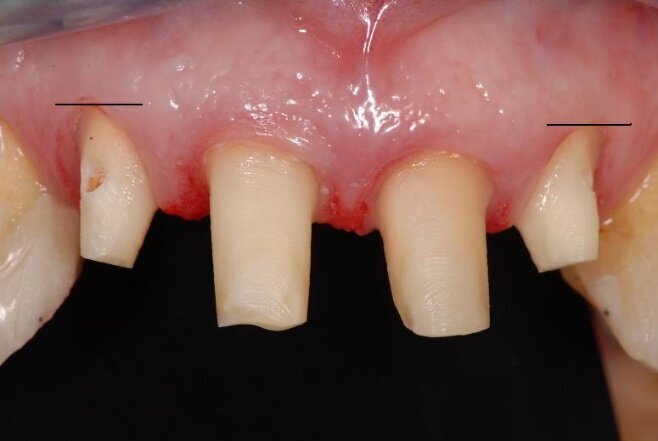

La paziente (che agirà in giudizio) 55 anni, fumatrice con scarso controllo dell’igiene domiciliare, in cura nel 1998 per parodontopatia cronica e compromissione dei quattro incisivi superiori (Figg. 1-5) per dodici anni, viene trattata con terapie chirurgiche e non2. Nel luglio 2010, dopo ben 12 anni di mantenimento di tali denti, si presenta all’osservazione dell’odontoiatra per la rottura dello splintaggio, riferendo di aver subito un accidentale trauma facciale.

Il dentista verifica un aggravamento della mobilità dei quattro incisivi e sollecitato dalla paziente a migliorare l’aspetto estetico, prospetta la sostituzione degli elementi naturali da estrarre, con una protesi fissa su impianti. Al fine di ridurre il rischio di un ulteriore riassorbimento dell’osso alveolare residuo e del collasso dei tessuti molli3-7 della pre-maxilla, prima delle estrazioni degli incisivi, viene prospettata la loro estrusione8, 9.

Tutto ciò viene dettagliatamente spiegato sia verbalmente, sia descritto nel “Consenso informato” che la paziente sottoscrive dopo aver richiesto un secondo consulto presso un altro studio. Il trattamento estrusivo dei due incisivi laterali inizia nel gennaio 2011 (Figg. 7, 8). Al raggiungimento del risultato desiderato (Figg. 9, 10), si attendono 60 giorni di “stabilizzazione” dell’osso alveolare18 (Figg. 11, 12).

La fase chirurgica viene pianificata con la preparazione iniziale (igiene orale, controllo emato-chimico delle condizioni della paziente, prescrizione della profilassi/terapia antibiotica19-20 e della sospensione del fumo). Il 23 giugno 2011, vengono estratti i due incisivi laterali (Figg. 13, 14) e inseriti contestualmente due impianti Xive (Dentsply) di diametro 3,8 mm e lunghezza 15 mm (Figg. 15, 16), dimensioni ottimali per la successiva protesi (ponte di 4 elementi da 1.2 a 2.2 con 1.1 e 2.1, elementi “intermedi”).